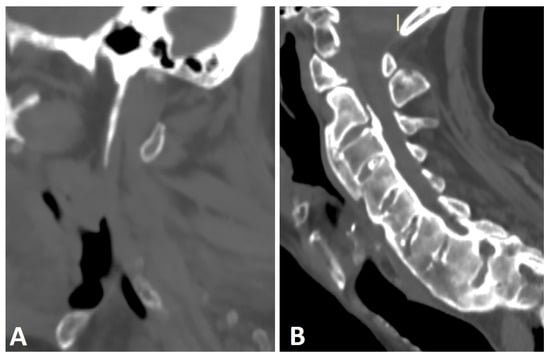

Anterior ossification of the spine in DISH may involve the cervical spine, primarily along the lower half of the anterior border of the vertebral body, forming a “candle flame” or “parrot-beak” image (Figure 2) [32]. These cervical flowing osteophytes are frequently asymptomatic but may result in dysphagia, sleep apnea, airway obstruction, and difficulty in intubation [7,23,33]. It has been reported that approximately one-third (33%) of subjects with DISH involving the middle or lower thoracic region have coexisting DISH in the cervical spine, according to whole-spine computed tomography (CT) [34].

Figure 2.

Sagittal CT reconstruction images of two patients with thoracic (not shown) and cervical DISH. (A) Flowing chunky osteophytes are located anteriorly to the vertebrae, forming a “candle flame” or “parrot-beak” image. (B) Thick, not-yet-flowing anterior osteophytes and thick posterior osteophytes at the C5–6 level.